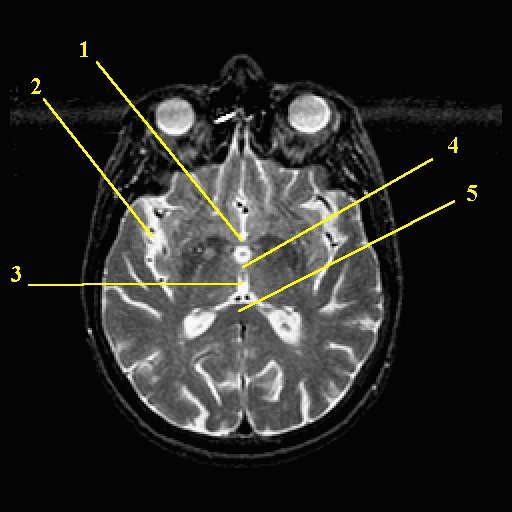

The next several pages will review the structures of the human brain. The images are MRI images and are from the Whole Brain Atlas.

On each page you will be shown an image labelled with numbers. The numbers refer to the text boxes on the form that you fill in with your answers. The smaller figure, either to the right or below the main figure, shows the level of the horizontal image in the brain. In addition, there is a study page which presents a labelled version of the same horizontal view of the brain.

1: 2:

3: 4: 5: